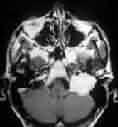

|

|

Orbital meningioma-CT

|

Parasagittal

meningioma-MRI

|